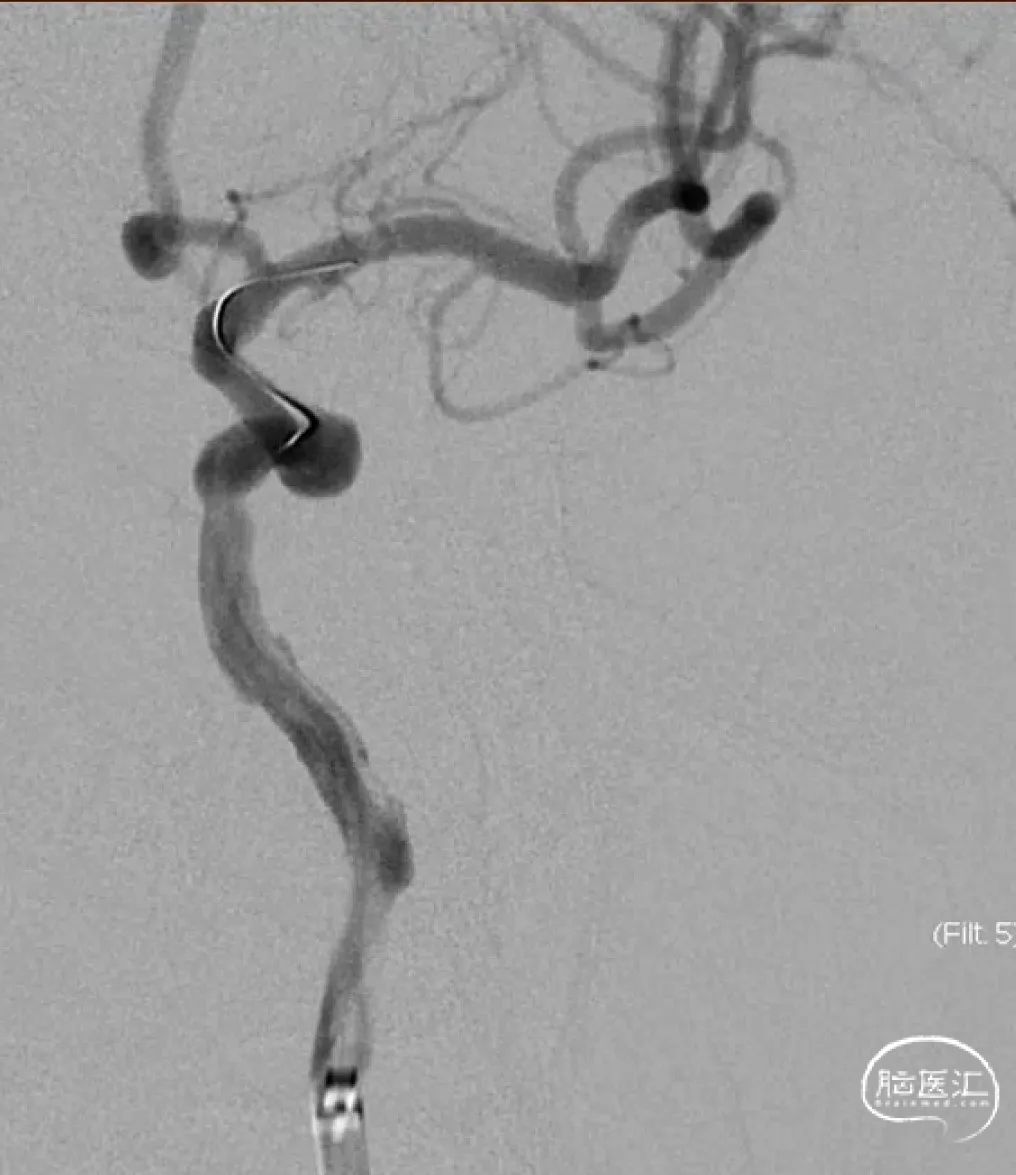

术前影像

右侧颈动脉造影

左侧颈动脉造影

左侧颈内动脉重建(左侧狭窄及扩张较右侧更甚)

扩张后再次复查造影示支架打开及贴壁较前明显改善

标准正侧位造影未见远端血管栓塞

稀释造影提示支架贴壁可,狭窄改善